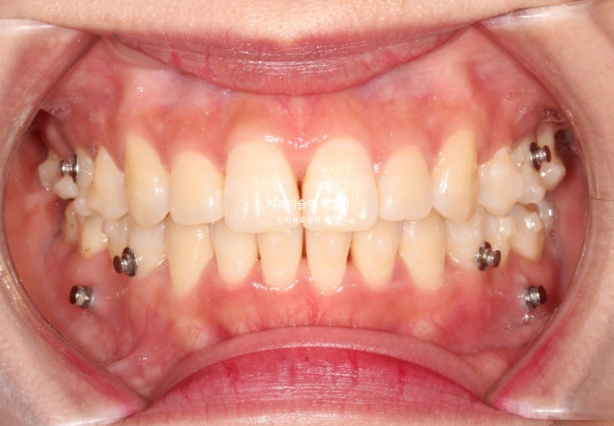

24년 8월부터 25년 4월까지 31개 추가장치를 모두 낀 후 모습입니다.

25.04

중심선은 잘 맞으나 앞니 사이 미세공간이 남아있습니다.

또한 위 앞니 사이 블랙트라이앵글도 눈에 띕니다.

발치공간은 깨끗하게 없어졌고

배열은 좋습니다.

쓰러졌던 큰어금니들은 잘 섰으나 한쪽 어금니 교합의 개선이 좀 더 필요합니다.

미세공간의 해결, 블랙트라이앵글, 어금니 교합 개선을 위해 두번째 추가장치 제작을 합니다.